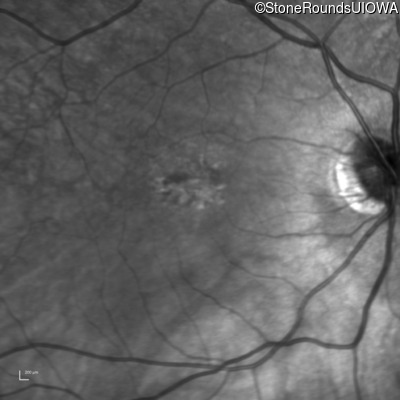

OD OS

Age at visit: 55 years

Age at visit: 56 years

Age at visit: 58 years

Age at visit: 59 years

The clinical features supporting the diagnosis of blue cone monochromacy in this patient include: stable reduced acuity, photophobia and very poor color vision since early childhood, a normal fundus appearance, normally sighted parents and three similarly affected male relatives on the maternal side of his family.